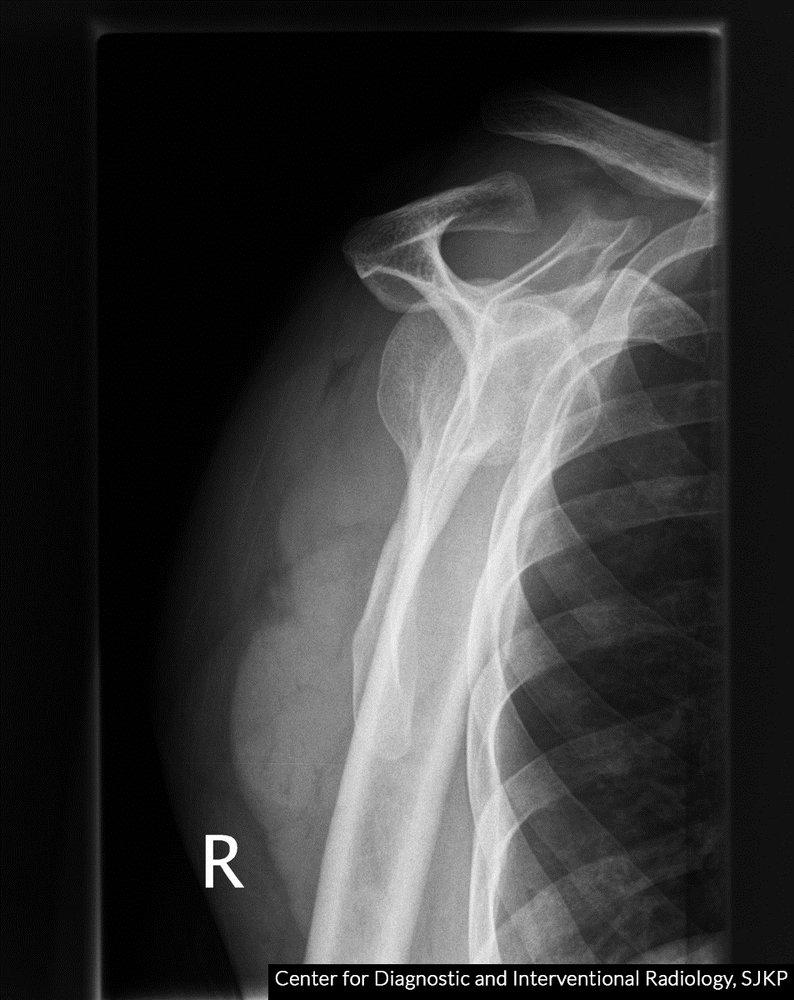

• X-ray (anterior-posterior view, oblique view, axillary view) of the shoulder joint, acromion, and scapula:

• Subluxation of the AC joint space

• Widening of the CC space

• Displacement of the clavicle

• Accompanying injuries (e.g., clavicle fracture)